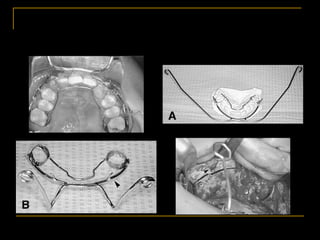

Passive Max obturator

 Passive prosthetic appliance

 Restores the palatal cleft

 Aids sucking

 Prevents maxillary arch from collapsing

 Made of cold cure or heat cure acrylic

 Extraoral clasps-for retention of the

appliance

 Held adjacent to the cheeks with

micropore adhesive tape

Infants with bilateral clefts –need 2 types

of movements of maxillary segment-

 Collapsed maxillary posterior segment

must be kept laterally

 Pressure against premaxilla to reposition it

posteriorly

Presurgical orthopaedics

Repositioning-

 By application of leucoplast over the

premaxillary segment

 With appliance pinned to the segments

 Early lip repair